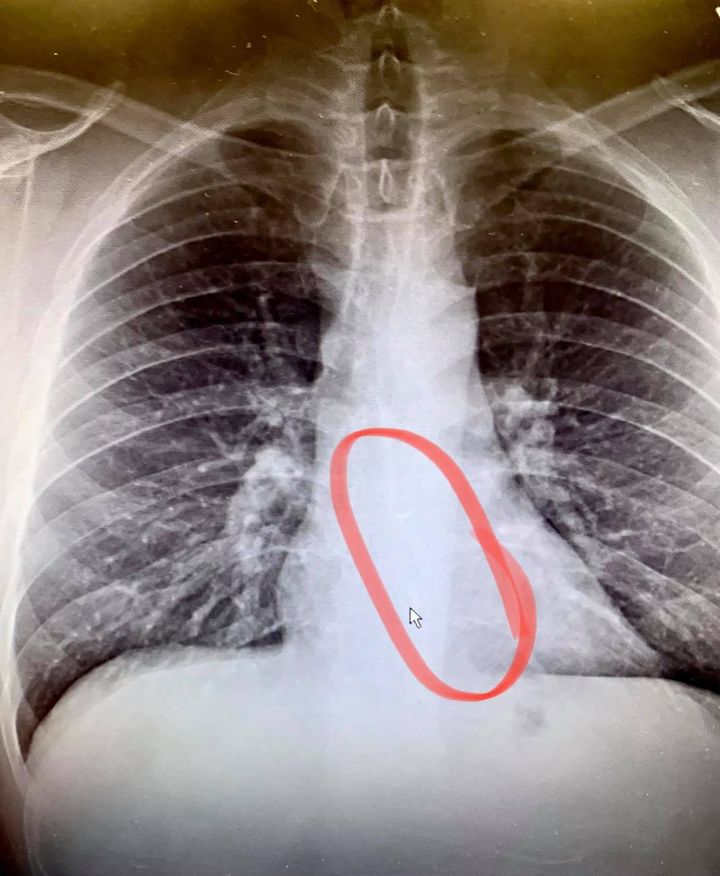

他越想越不對勁,立即前往求診,醫生為他一照X光,果然發現他遺失的耳機卡在食道中,疑似是睡著後誤將無線耳機吞下。醫生於是透過內視鏡將耳機夾出來,現已無大礙。事後他提醒睡覺時使用無線耳機要注意,要以他為鑑。